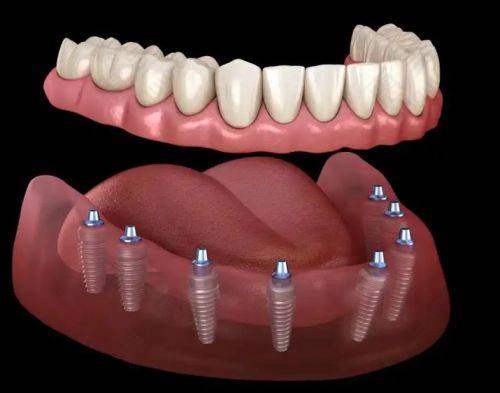

在服务项目方面,丰台院区提供了完善的口腔医疗服务。涵盖了日常口腔护理,像牙齿清洁、牙结石去除、牙齿美白等;牙齿修复项目,如补牙、牙冠、牙桥等;牙齿矫正服务,包括隐形矫正、传统矫正等;还有种植牙服务,为牙齿缺失患者带来福音。此外,医院还设有多个口腔科室,如口腔颌面外科、牙周科、儿童口腔科等。

海淀院区同样提供全方面的口腔医疗服务,包括日常口腔护理、牙齿修复、牙齿矫正、种植牙以及各类口腔科室的服务。患者反馈海淀院区的医生态度友好,服务周到,设备齐全,在治疗过程中患者能感到舒适。其营业时间为周一至周日08:30 - 17:30 ,方便患者随时就诊。